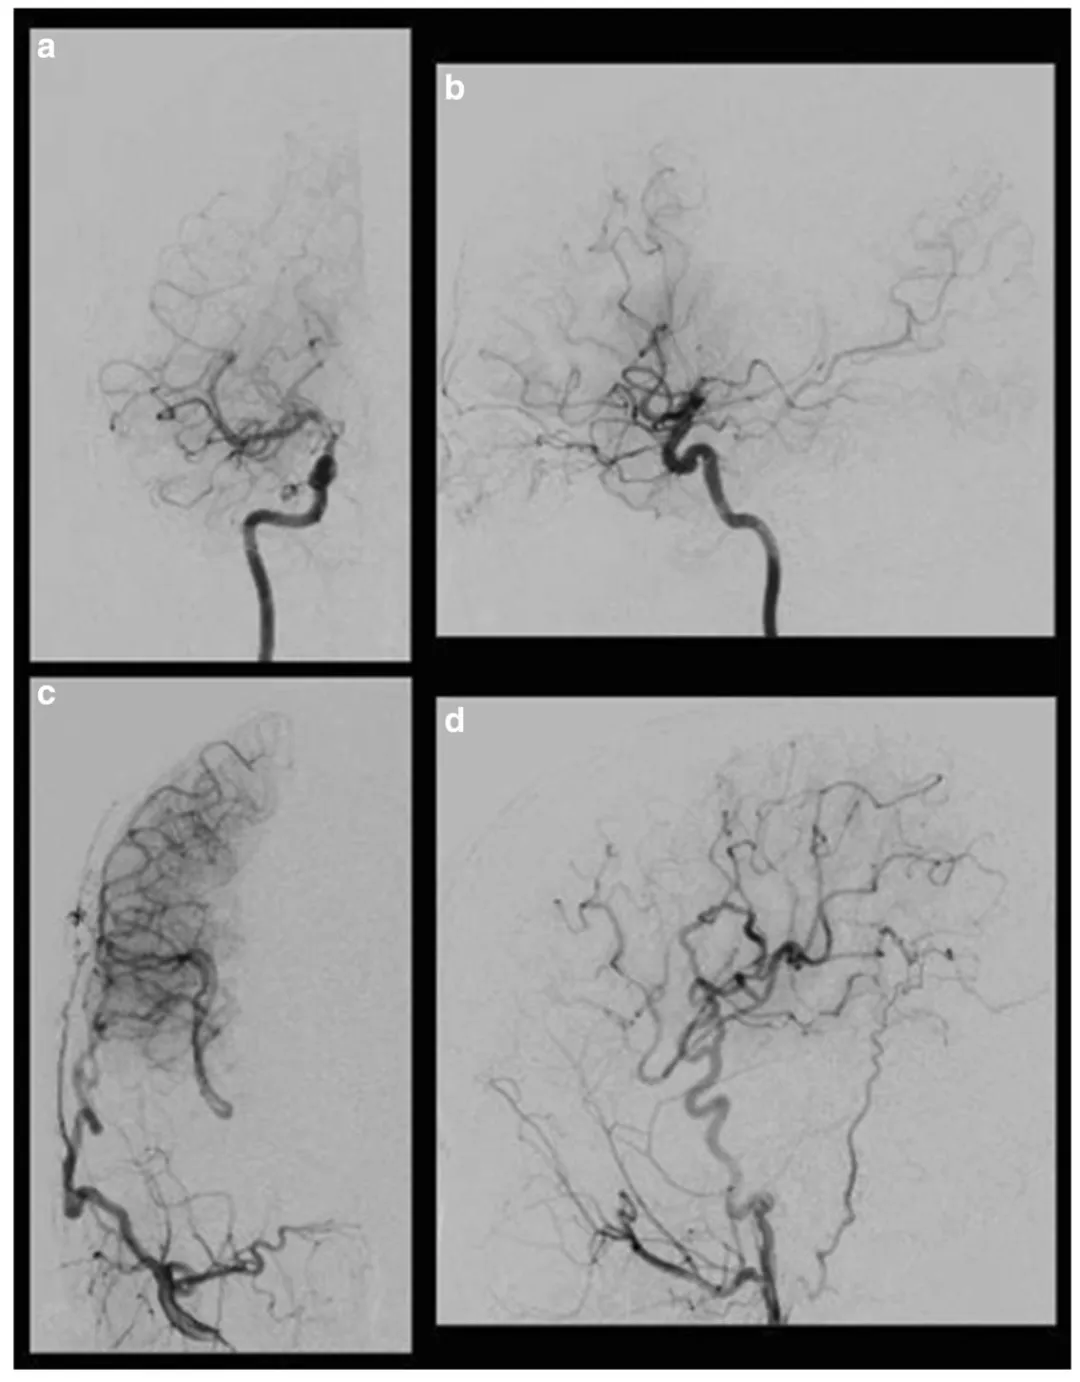

术后右侧颈动脉血管造影显示,通过右侧颈外动脉的搭桥血管向大脑中动脉(MCA)和大脑前动脉(ACA)供血不足区域供血。右侧颈内动脉正位观(a)和侧位观(b);右侧颈外动脉正位观(c)和侧位观(d)

术后7个月的复查结果进一步验证了手术效果:血管造影清晰显示,新搭建的搭桥血管通畅良好,颈外动脉的血流通过搭桥血管,持续稳定地供应到右侧大脑中动脉及大脑前动脉供血不足区域,从根本上改善了脑组织血液灌注,成功阻断了病情进展。